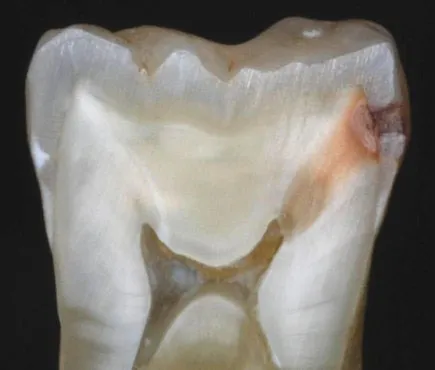

ฟันผุต้นเหตุโรคฝีในสมอง ฟันผุไม่ได้ทำร้ายแค่ฟันเพียงอย่างเดียวแต่ยังทำร้ายไปถึงสมองด้วยซึ่งถือว่าเป็นอันตรายอย่างมาก การที่เราปล่อยให้ฟันผุเป็นเ...